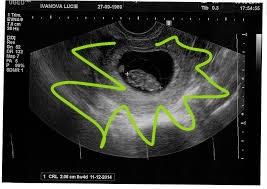

@jaja875 a test je pozitívny? Nemusela nič vidieť ak bola posunutá ovulácia. Ja som bola po viac ako troch týždňoch od predpokladanej ms u dr a videla len gestacny a žĺtkový vak. Takže je stále možné že tehotná ste

@jaja875 mne menzes meškal 19 dní a doktorka na ultrazvuku nevidela nič.. Testy som mala pozitívne.

@alica_matejka neviem no nevidela nič.. Az o ďalší týždeň som prišla na ultrazvuk a bolo vidno vak.. Ale ja som mala nepravidelný menzes.. Každý mesiac stále inak..